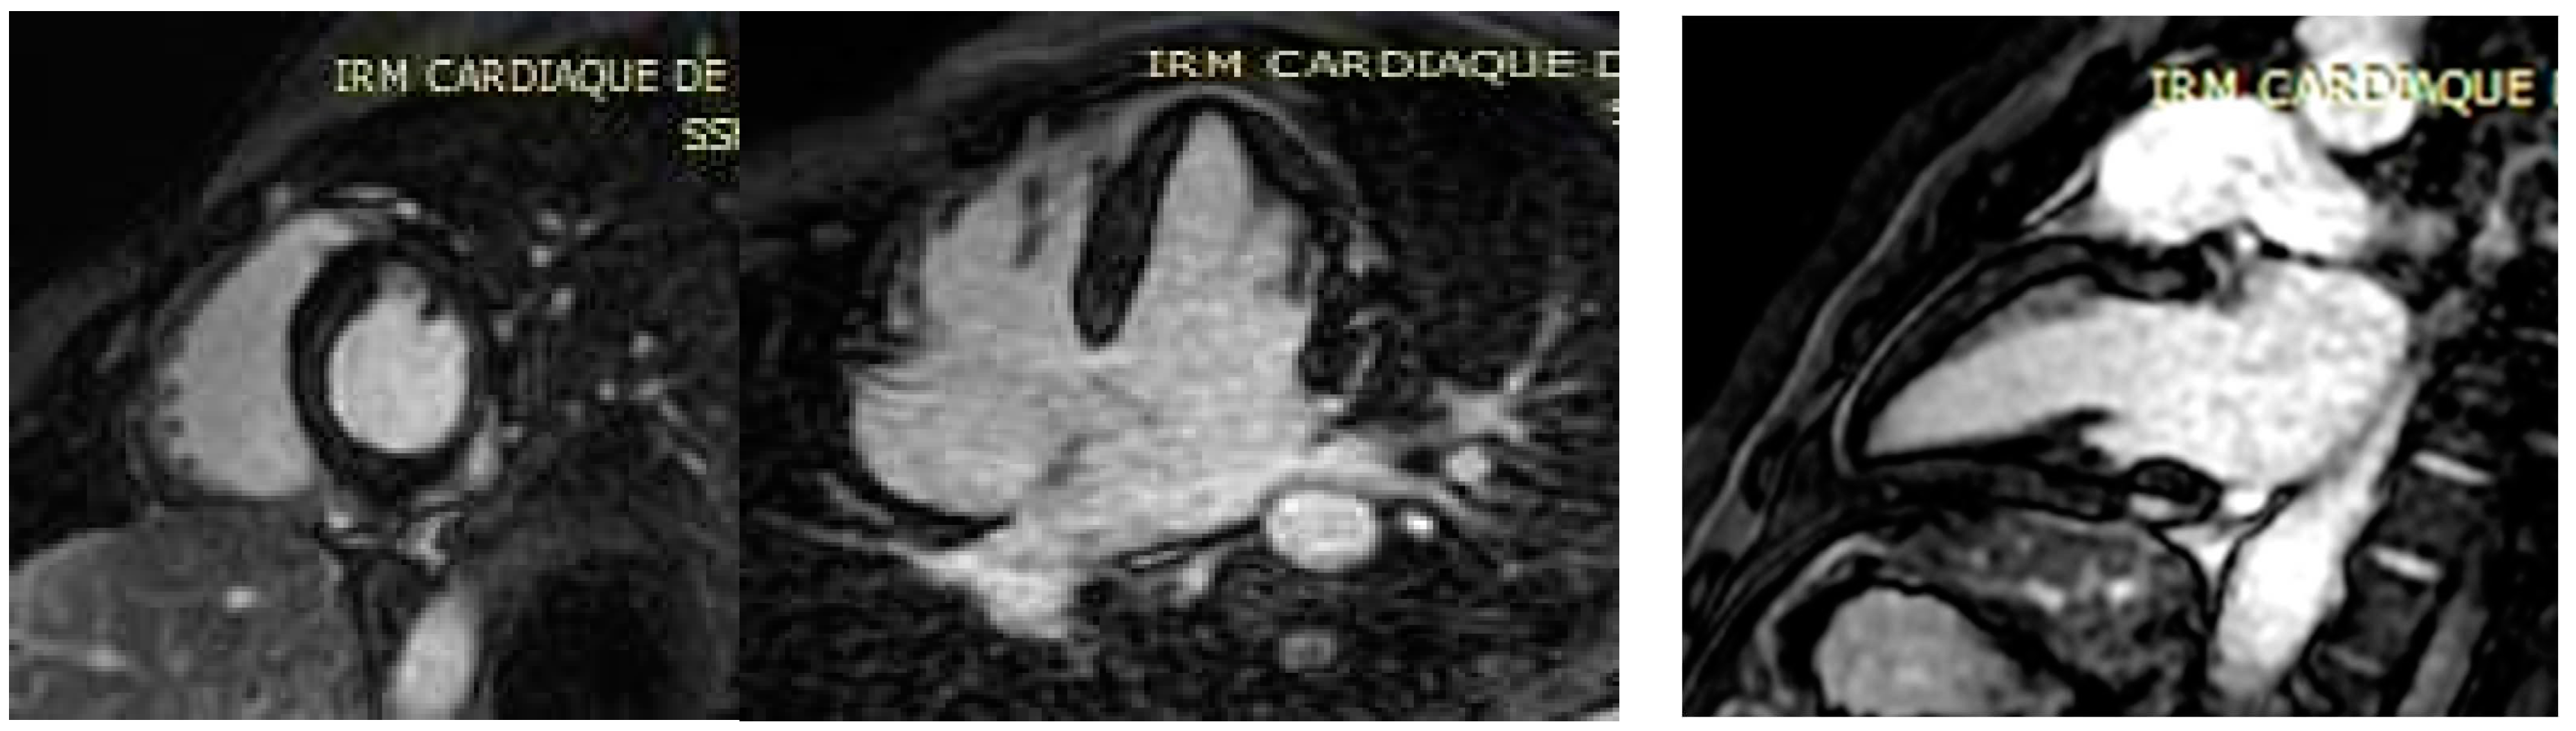

A 23-year-old male patient without past medical history presented to the emergency room with recent retrosternal chest tightness and pain. He reported recent gastro-intestinal (GI) symptoms of nausea, vomiting, 4-day watery diarrhea with transient episode of fever (38.7 °C). At admission, physical examination showed an impaired general status. He was afebrile (37.2 °C), respiratory rate 20 per min., cardiac assessment showed blood pressure of 140/70 mmHg, regular tachycardia of 100 beats per minute and normal cardiac murmur. Pulmonary examination showed a respiratory rate of 16 cycles per min, and auscultation was normal. He denied abdominal pain, and palpation showed no tenderness and no liver or spleen enlargement. He reported generalized myalgia but rheumatological evaluation did not show arthritis or productive myalgia. The electrocardiogram (ECG) showed left axis deviation with regular sinusal tachycardia. Routine laboratory showed leukocytosis 13 G/L (normal range < 10 G/L), neutrophilia 8.2 G/L (normal range 1.5–7 G/L) and lymphopenia 600/mm3 (normal range 1500 to 4000/mm3) on cell blood count, with elevated C-reactive protein of 130 mg/dL (normal range < 5 mg/dL), serum electrolytes, creatinine and liver enzymes within normal limits. Maximum Troponins and creatine kinase MB (CK-MB) were elevated to 678 ng/L (normal range < 14 ng/L) and 54 ng/mL (normal range < 7 ng/mL). The patient was admitted to the cardiac department for further workup. He was managed symptomatically with analgesics, anti-reflux and fluids. Transthoracic echocardiography (TTE) revealed a preserved ejection fraction (EF) of 55% with normal wall motions, no valvular dysfunction, normal pulmonary pressure and no pericardial effusion. His risk of coronary artery disease (CAD) was low; moreover, clinical, biological and echocardiographic presentation summed the hypothesis of an acute myocarditis. A large etiological workup, including repeated peripheral blood culture, Mycoplasma pneumoniae, Chlamydia pneumoniae, Coxiella burnetii, Borrelia burgdorferi, Leptospira spp., Rickettsia spp. and Brucella spp., was conducted. The serologies, such as urinary Legionella pneumophila antigen, were negative. Moreover, serologies of RNA viruses (coxsackieviruses A and B, hepatitis C virus, human immunodeficiency virus) and DNA viruses (adenoviruses, parvovirus B19, cytomegalovirus, human herpes virus-6, Epstein-Barr virus, varicella-zoster virus and herpes simplex virus) were negative. Autoimmune assessment, including antinuclear, anti-neutrophil cytoplasmic antibodies, systemic sclerosis and autoimmune myopathies specific antibodies and converting enzyme assay, were negative. The patient denied any recent drug intake. A Gram stain of specimen stool collected showed multiple curved and spiral Gram-negative rods. Biochemical tests indicated an oxidase, catalase and hippurate negative and indoxyl acetate-positive bacterial species, corresponding to C. jejuni. Stool cultures confirmed the diagnosis of C. jejuni sensitive to macrolides (Azithromycin/Roxithromycin/Clarythromycin) and flouroquinolones (Ciprofloxacin). Continuous telemetry monitoring showed some runs of non-sustained ventricular tachycardia (NSVT). Oral bisoprolol 2.5 mg twice daily was started for that, and oral 1 g of Azithromycin was administered. He remained clinically stable over the rest of the hospital course, and the diarrhea was progressively resolved. The patient remained stable, and we could perform cardiovascular magnetic resonance (CMR) imaging. Triple inversion-recovery black-blood T2-weighted STIR sequences showed focal areas of hypersignal in the subepicardium of the posterolateral left ventricular (LV) wall, indicative of myocardial edema (Figure 1). In addition, steady-state-free-precession (SSFP) cine CMR showed early hypersignal in the subepicardium of the posterolateral LV wall immediately after injection of 0.1 mM of Gadolinium chelates, indicating focal hyperemia (Figure 2). Inversion-recovery gradient-echo-based late Gadolinium enhancement techniques, acquired 10 min. after Gadolinium injection, revealed subepicardial nodular lesions of myocardial damage (Figure 3). The final diagnosis of C. jejuni-related acute myocarditis was supported by the Lake Louise criteria [7]. The patient was discharged free of symptoms after one week in hospital. On close follow-up, his C-reactive protein and cardiac enzymes normalized after three weeks. Repeated TTE and 24-h ECG were normal, so bisoprolol was progressively discontinued after 6 months. Control CMR imaging at 3 months showed regression of the focal areas of hyper signal in the sub epicardium of the posterolateral left ventricular (LV) wall.

Figure 1. Black-blood edema-sensitive T2 STIR images showing subepicardial posterolateral hypersignal (arrows) indicative of focal edema in the short axis and the 2-chamber view of the left ventricle.